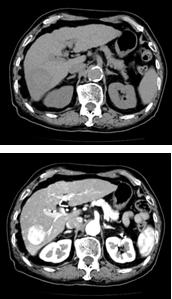

| CT検査では水溶性ヨード造影剤が用いられます。通常腕の静脈より投与され、血管を介して全身の臓器へと分布します。この分布により病気や各臓器の血流状態や血管の情報を得ることができます。造影剤を使用しなくても検査は実施できますが、病気の存在が分かりにくく正確な診断ができないことがあります。右の図は造影剤を使用する前と使用した後の画像です。この検査では血管の流れや病気、臓器の状態をわかりやすくすることができます。 一方、ヨード造影剤が投与されると体内はバランスを保とうとするはたらきが作用し、どなたにも熱感や疼痛が起こります。また、安全な薬ですが使用後にまれに副作用が生じることがあり、使用後すぐに起きる場合と、数時間から数日経ってから発生する場合があります。副作用の種類は、軽度なものは吐き気・かゆみ・発疹・動悸、重度なものは呼吸困難・血圧低下・意識障害などがあります。仮に副作用や合併症が生じた場合は、医師や看護師が直ちに適切な処置を行います。少しでも異常を感じた場合は遠慮なく担当者へお知らせください。また数日後に発生した場合でも適切な治療を行いますので、医療機関にご連絡ください。 |